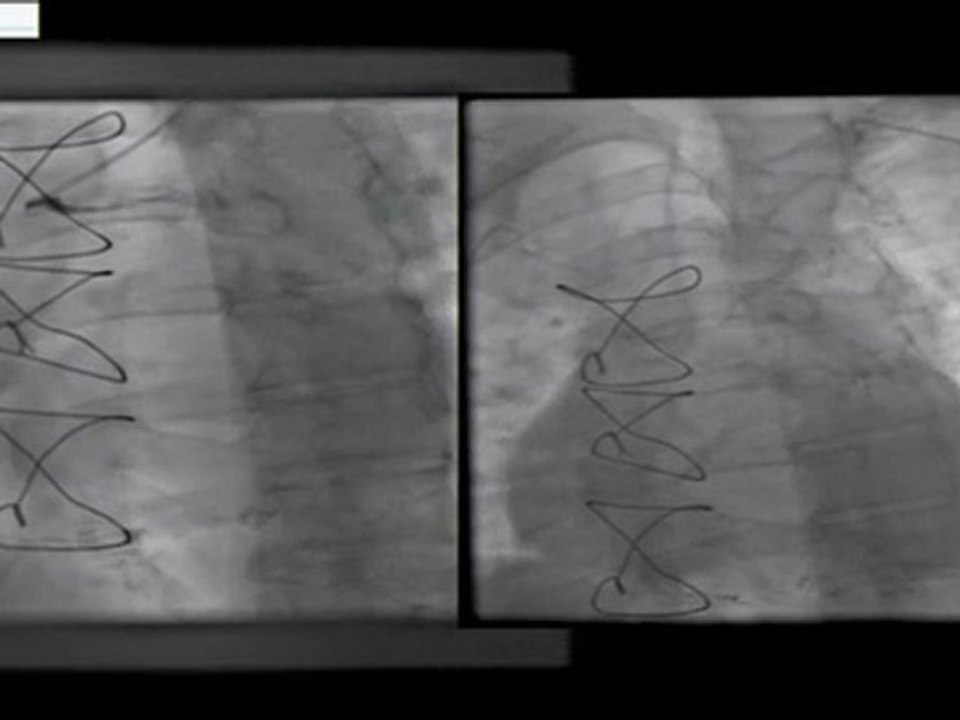

10 tibio-peroneal artery atherectomy (rotablator) antegrade approach incathlab.com